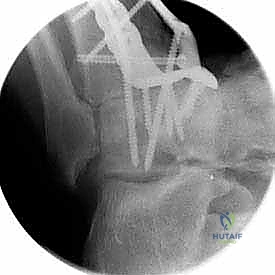

تثبيت مفصل الكاحل، أو "دمج الكاحل" (Ankle Fusion)، هو إجراء جراحي عالي التخصص يهدف إلى تحويل مفصل الكاحل المريض والمؤلم إلى كتلة عظمية واحدة صلبة وغير متحركة. الفلسفة الطبية وراء هذا الإجراء بسيطة وفعالة: "مفصل ثابت وبدون ألم أفضل بكثير من مفصل متحرك يسبب ألماً مبرحاً".

- تثبيت ميكانيكي حيوي أقوى: يتيح المدخل الأمامي وضع شريحة معدنية (Anterior Plate) على الجانب الأمامي للمفصل. من الناحية الميكانيكية الحيوية (Biomechanics)، يعتبر الجانب الأمامي هو "جانب الشد" (Tension side) أثناء المشي. وضع الشريحة هنا يوفر تثبيتاً فائق القوة ويقلل من معدلات عدم الالتئام.

- التخطيط الجراحي الرقمي: باستخدام صور الأشعة المقطعية، يقوم الدكتور هطيف بتخطيط الجراحة على الكمبيوتر لاختيار حجم المسامير والشرائح المناسبة بدقة مليمترية.

خطوات جراحة تثبيت مفصل الكاحل الأمامي بالتفصيل (Step-by-Step Surgical Procedure)

تُجرى العملية تحت التخدير العام أو النصفي (الشوكي)، وتستغرق عادةً بين ساعتين إلى ثلاث ساعات، وتتطلب دقة ومهارة فائقتين. إليكم الخطوات الجراحية كما ينفذها الأستاذ الدكتور محمد هطيف: